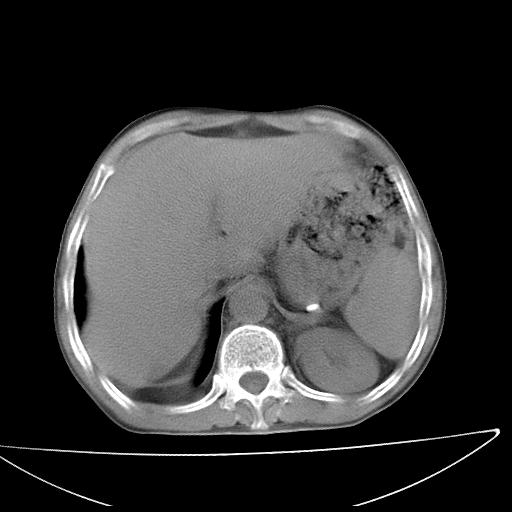

男  70岁,发烧咳嗽4天。盗汗,消瘦。无痰中带血丝,以前有肺tb病史,ct见,双肺tb,左侧胸廓塌陷,左胸膜肥厚粘连。纵隔移位,右侧胸腔积液,大家说说那个心影前左肺舌叶除了肺大炮还有炎症还是干酪性肺炎?有占位吗?我看纵隔淋巴结也大。

是胃,纵膈未见明显肿大淋巴结。